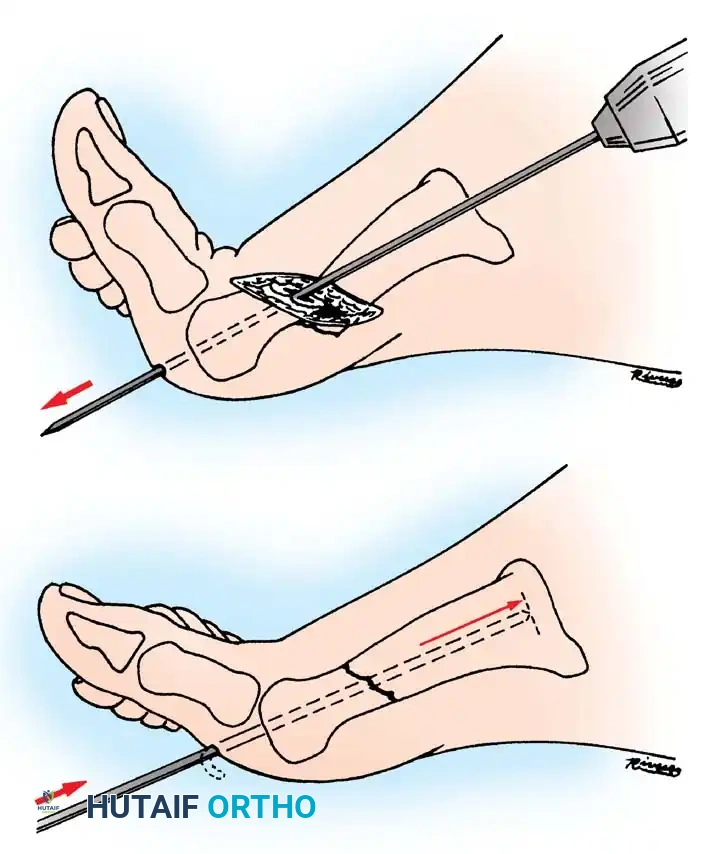

Posterior to Anterior Fixation:

As a biomechanically superior alternative, a cancellous lag screw can be inserted percutaneously from posterior to anterior. This requires a posterolateral approach, taking extreme care to protect the sural nerve and the flexor hallucis longus (FHL) tendon. Posterior-to-anterior screws cross the fracture site perpendicular to the primary fracture plane, offering enhanced compression.